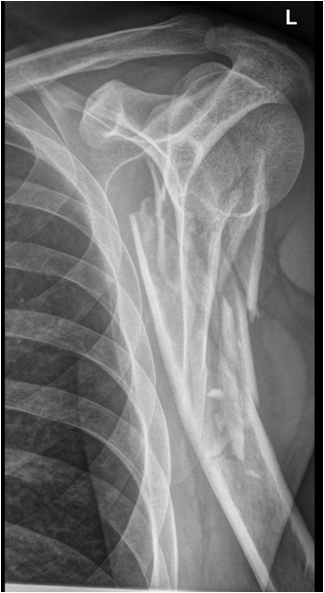

Fig. 8. Diagram showing different types of fractures: fissure or incomplete fracture, transverse simple fracture, oblique simple fracture, spiral fracture, simple and complex comminuted fracture. The x-ray example shows a severely comminuted fracture of the proximal humerus. Note that the angulation of the facture with 30-degree dorsal tilt of the distal fragment is fully seen only on the transscapular view (second plane).